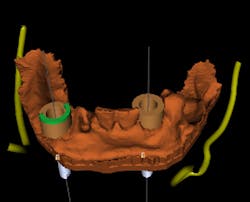

A polyvinyl siloxane (PVS) impression is taken of the remaining mandibular teeth. A CBCT scan is taken of the patient without a scan guide, and a CBCT scan is taken of the PVS impression in the mouth. The impression scan can be inverted and aligned with the patient’s CBCT scan in the implant planning software. This gives an accurate digital representation of the bone as well as the dentition (figure 2).

Figure 2: CBCT image

A stable guide can rest on just two teeth, and also can take some tissue support if necessary. The implants can be placed as immediate implants, provided enough teeth remain to support the guide. In this case, the right lateral (No. 26) is virtually extracted and implants are planned for sites Nos. 23 and 26. A tooth-supported guide is designed and 3-D printed (figure 3).

Figure 3: Surgical guide